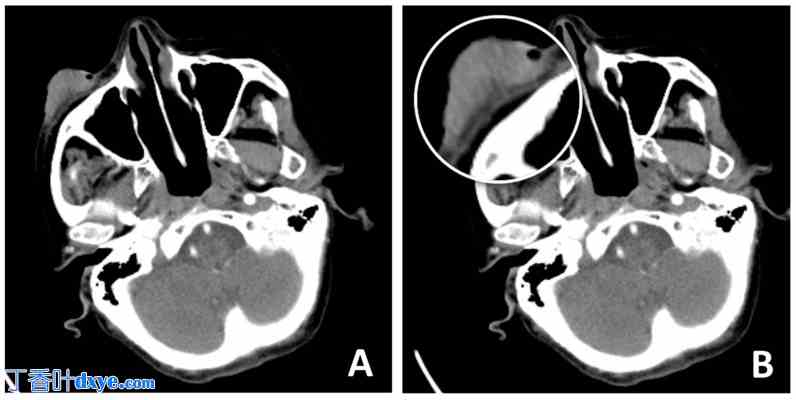

一位93岁的女性患者就诊,诉其右下眼睑肿瘤近10年呈扩张性生长,无疼痛症状,3个月前发现病灶加速生长。检查发现右下眼睑有一直径4厘米的溃疡性病灶,并延伸至颧骨区域(图1A、B)。在仔细考虑了各种重建方法后,作者选择采用Mohs显微手术切除肿瘤病灶,并采用Mustarde颊部旋转推进皮瓣缝合剩余缺损。患者15年前曾患缺血性卒中,并有NYHA心功能分级II级心力衰竭病史,目前已接受药物治疗。在评估麻醉风险并停用口服抗凝剂治疗后,患者被认为适合择期手术。术前行CT扫描以评估周围组织的受累情况(图2A、B)。

图 2.

2.jpg

(A,B) CT 扫描显示肿瘤侵袭软组织,直至前眼睑板层,可能已侵袭眶隔。(B) 下层骨组织看似完整。病变以扩张性而非浸润性为主。